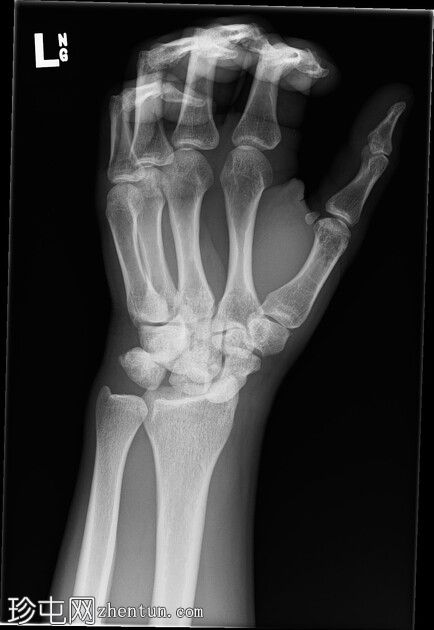

左腕

X光片

斜位

前后位:舟月骨间隙明显增宽,月骨呈三角形。侧面显示月骨掌侧脱位,头状骨和桡骨远端保持正常排列,符合月骨脱位。陈旧性背侧三角骨骨折。腕部软组织肿胀。